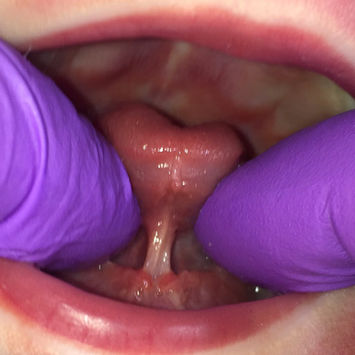

Research suggests that approximately 1 in 10 babies may be born with some membrane under the tongue. But only about half of those babies display significantly reduced tongue function, making infant feeding difficult.

These babies are likely to benefit from treatment to release the restriction that the membrane is having on the tongue and enable to baby to feed effectively.

Release of tongue-tie procedure

All images copyright Suzanne Barber.